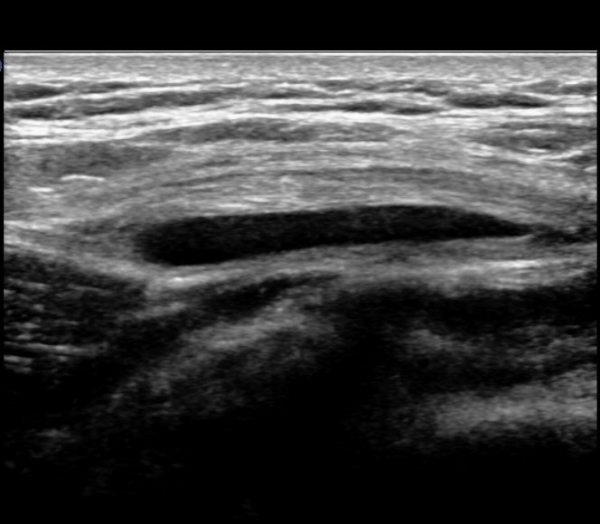

ŽÃËÀÚ¸¦ ¾ÕÂÊÀ¸·Î À̵¿ÇÏ¿© ´ëÀüÀÚ ¾ÕÂÊ È¾´Ü¸é°Ë»ç¿¡¼­ ¼ÒµÐ±ÙÈûÁÙ°ú Àå°æÀÎ´ë »çÀÌ¿¡

¼Ò·®ÀÇ ¼ö¾×Àú·ù°¡ °üÂûµÇ°í(»çÁø 4)

ŽÃËÀÚ¸¦ ¸Ó¸®ÂÊÀ¸·Î À̵¿ÇÏ´Ï ¼ö¾×Àú·ù°¡ ´õ ¸¹ÀÌ °üÂûµÈ´Ù(»çÁø 5).